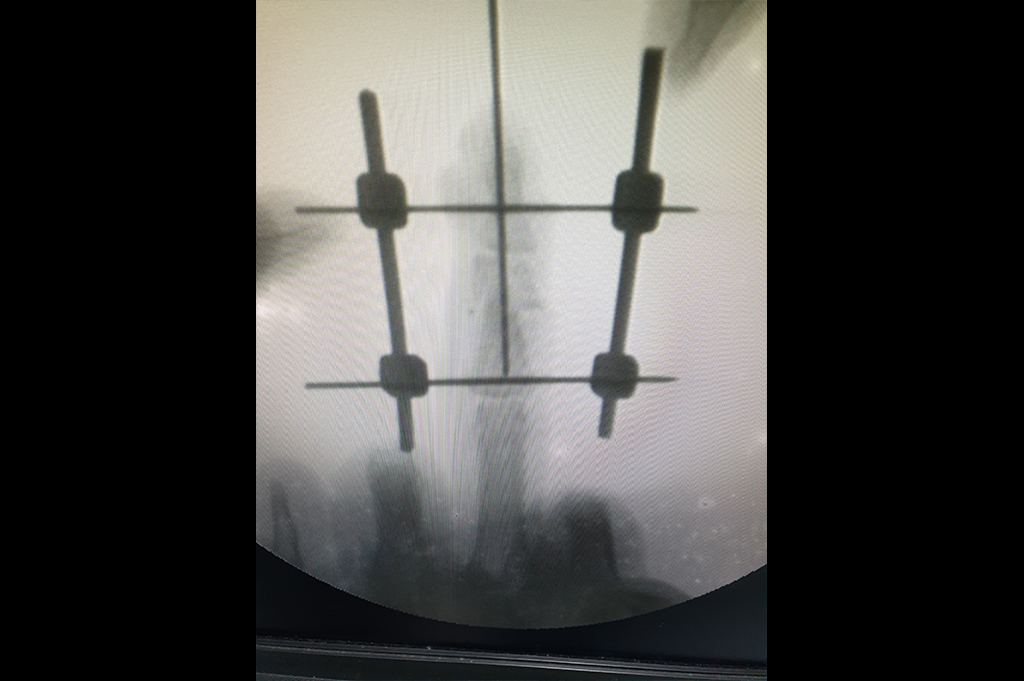

Finger Tip Injury - JESS